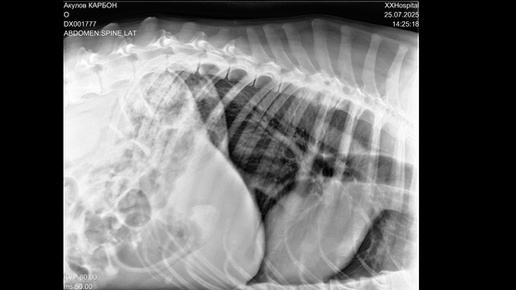

Здравствуйте. Нужен совет специалиста. За 5 дней у собаки отказали задние лапы. 1 День. Вечером не хотел гулять. Пройдет 50 метров, сядет - " Не пойду дальше". Аппетита нет. 2 День. Заметил что начали заплетаться задние лапы и неустойчивая походка. Поел. 3 День. Начал с трудом вставать. Погуляли, вроде расходился. Лапы так же заплетаются. Аппетит хороший. 4 День. Еле встал, вообще никуда идти не захотел. 5. День. Больше на задние лапы не вставал. Поехали в 1 клинику, сделали УЗИ брюшной полости. В пределах нормы...